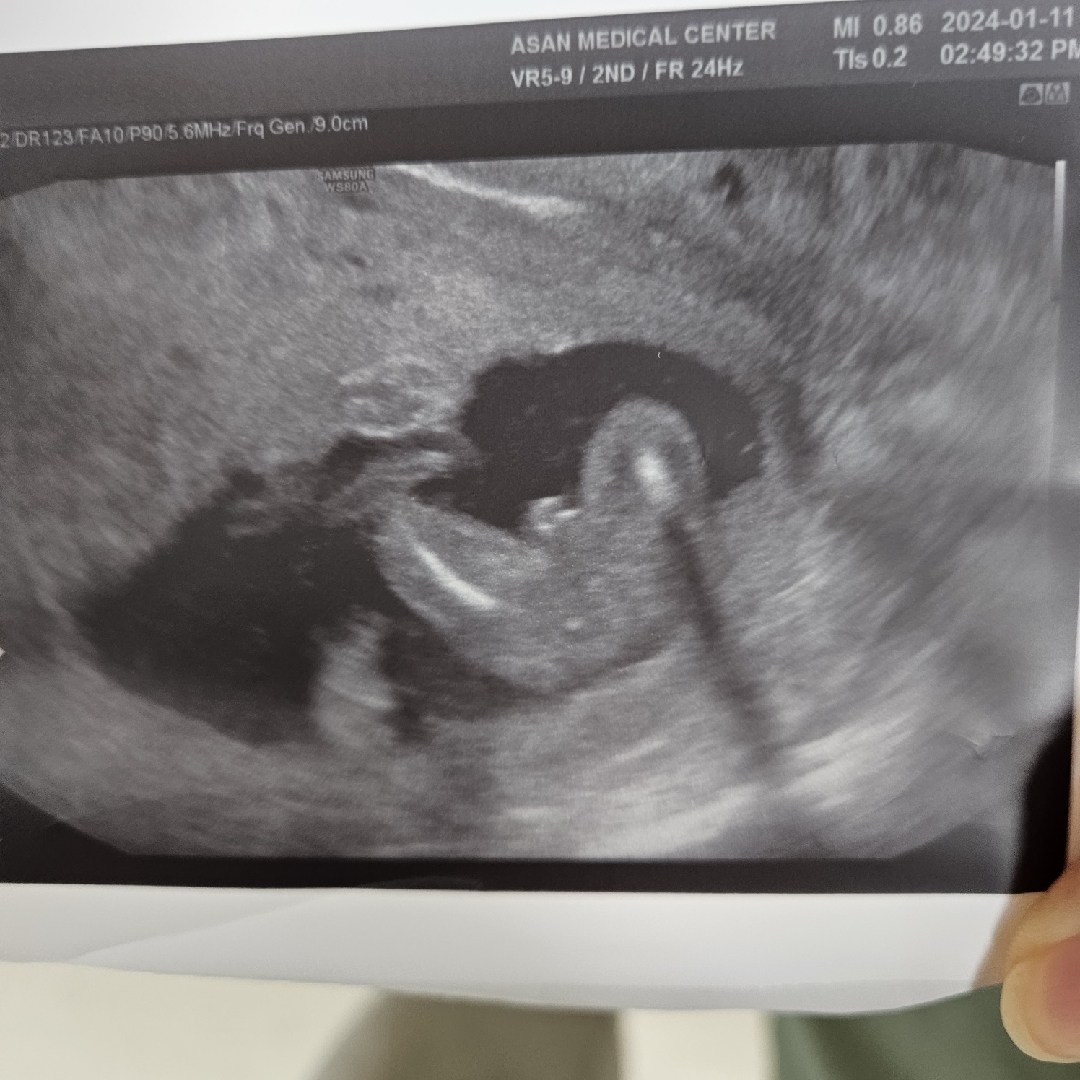

선생님이 이정도면 반전은 없을거같다고 하시긴 했는데 아들 확실할까요? 16주 2일차 사진입니당